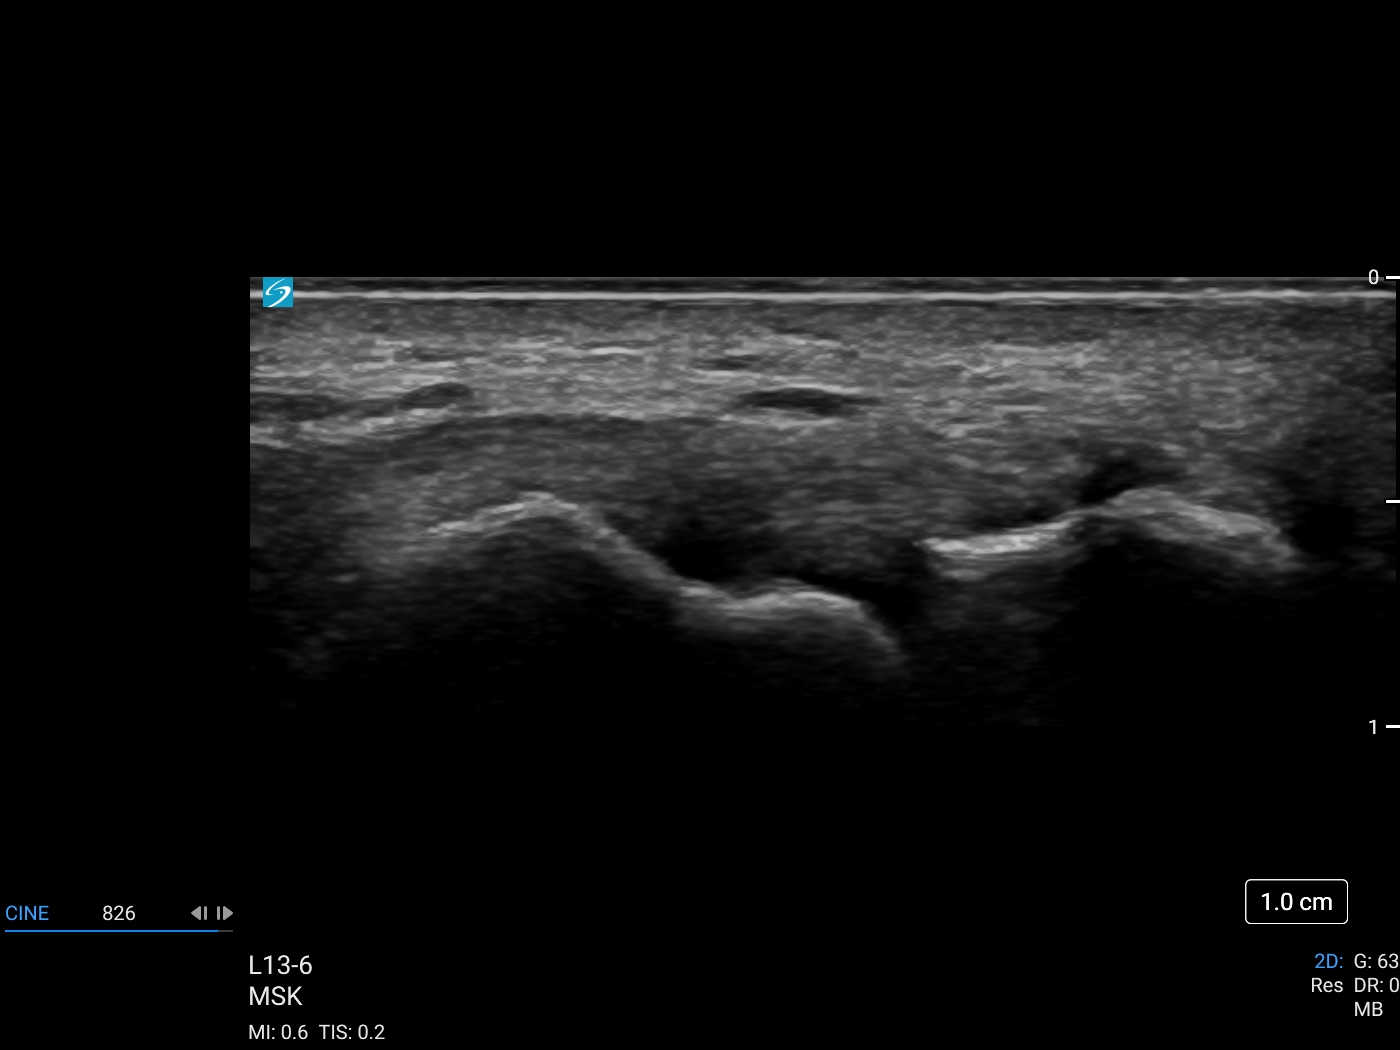

Ulnar Collateral Ligament with L13 hockey stick-6Mhz